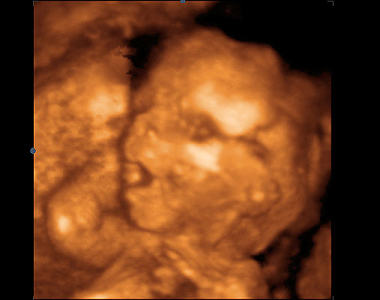

Plod 21. týden těhotenství. Pohled z boku dokumentuje vyrovnávání disproporcí mezi mozkovou a obličejovou částí hlavičky. Nejdelší šipka označuje čelo, před ní krátká nosní kůstku a spodní šipka ukazuje na horní čelist. Tento týden je vhodný k provádění II. ultrazvukového screeningu. V oblasti zad se ostře rýsují jednotlivé obratle.